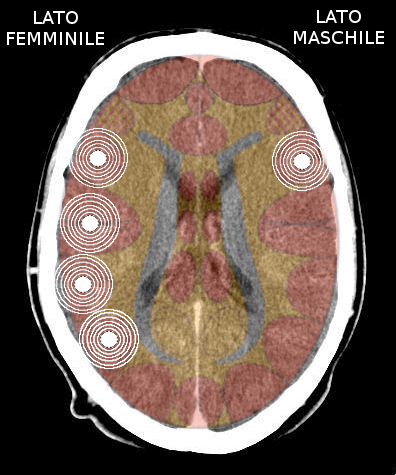

- Insula destra = ormonalità, percettività e comportamento maschile, sia nella femmina che nel maschio, destrimane o mancino. Quando attivata causa tonalità depressiva;

- Insula sinistra = ormonalità, percettività e comportamento femminile, sia nella femmina che nel maschio, destrimane o mancino. Quando attivata causa tonalità maniacale.

L'avvio di una attivazione territoriale, deprime l'ormonalità dell'emisfero colpito.

- Attivazione → lobo temporale destro = calo del testosterone (maschile); diminuisce il percepito maschile, la persona si deprime (perde aggressività);

- Attivazione → lobo temporale sinistro = calo dell'estrogeno (femminile); diminuisce il percepito femminile, la persona diventa maniacale (acquista aggressività).